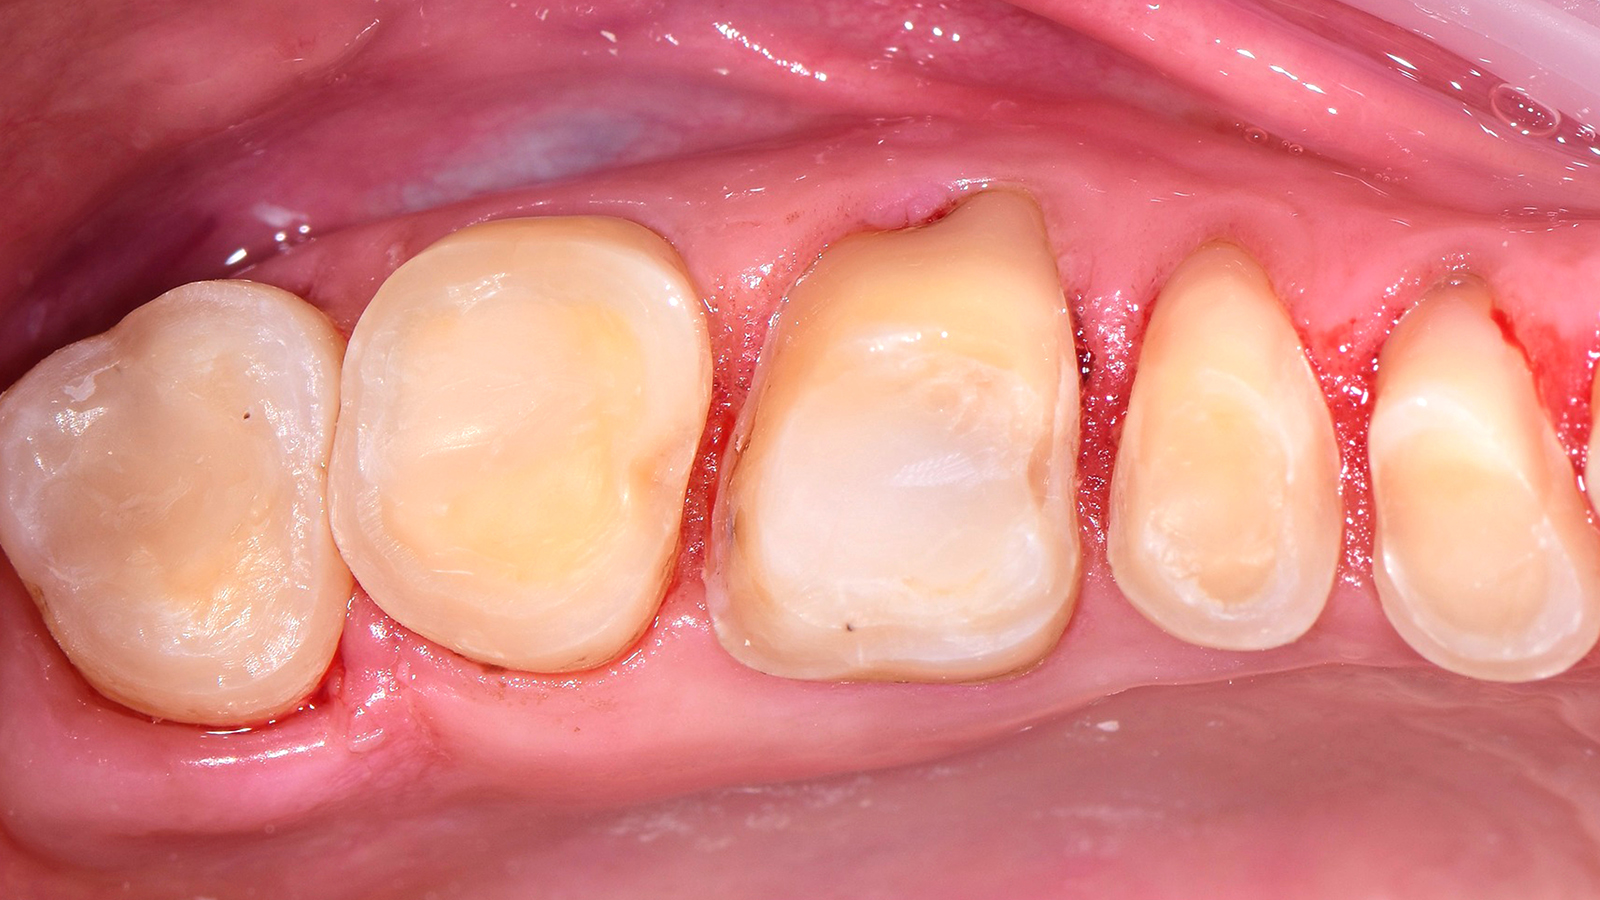

In case of severe discolourations, the tooth-coloured opaque shade Charisma Opal Flow OM (Opaque Medium) can be used. Alternatively, the white-opaque Charisma Opal Flow Baseliner can be used at the bottom of the cavity. This allows the coverage of discolourations and pre-vents the unnecessary removal of healthy tooth substance in case of a re-entry.

When is Charisma Bulk Flow ONE recommended to be used with or without capping lay-er?

Using Charisma Bulk Flow ONE without capping layer is beneficial in all clinical cases where a flowable viscosity is ideal during placement, e.g. slot or small cavities or those with tunnel preps, class III restorations with intact labial wall or class V restorations. From a patient perspective, Charisma Bulk Flow ONE is furthermore ideal in cases with little patient compliance or time. By preference or if patients demand a natural morphology, Charisma Bulk Flow ONE can always be used with capping layer, too. Using Charisma Classic, Charisma Diamond or Charisma Topaz on top might be advisable in big cavities or cusp replacements.